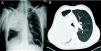

Varón de 45 años, fumador de 65 paquetes/año, diagnosticado de esquizofrenia. Ingresó por anorexia, astenia, febrícula y pérdida de peso en los últimos tres meses, además de disnea a ligeros esfuerzos. Dos meses antes había iniciado un cuadro de debilidad muscular progresiva generalizada en forma ascendente, con incapacidad para la marcha en la última semana. A la exploración física destacaba abolición del murmullo vesicular en los 2/3 superiores de hemitórax derecho, tetraparesia intensa de predominio proximal 1/5 y distal 2/5 con arreflexia universal y amiotrofia generalizada con sensibilidad conservada. La radiografía de tórax posteroanterior y lateral (fig. 1A) mostró una masa de contornos bien definidos que ocupaba el lóbulo superior derecho (LSD). Se realizó tomografía axial computarizada de tórax (fig. 1B) que confirmó la presencia de una masa pulmonar de 15×11cm en LSD, con infiltración de la arteria pulmonar derecha, compresión de la tráquea y adenopatías patológicas en mediastino. La fibrobroncospia reveló obstrucción del bronquio del LSD con infiltración tumoral, siendo el broncoaspirado, cepillado y biopsia bronquial compatibles con carcinoma microcítico. El electromiograma mostró hallazgos neurográficos compatibles con síndrome de Guillain Barré y los anticuerpos anti Hu, anti Yo, anti Ri, y anti canales de calcio fueron negativos. Se inició tratamiento con quimioterapia e inmunoglogulina intravenosa con mejoría progresiva de la clínica neurológica durante 15 días. El paciente falleció a los tres meses por progresión tumoral.